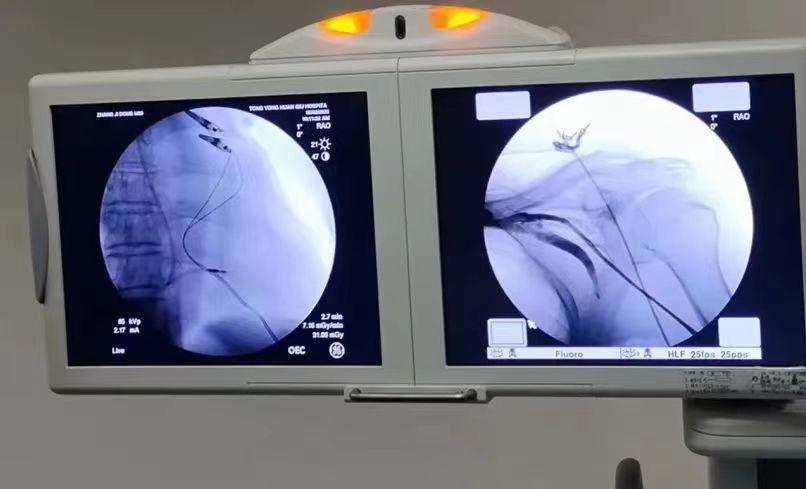

患者为普大型心脏,手术难度大、风险系数高。手术过程中,耿蓬勃与陈文璐两位副主任医师一边精细而娴熟的操作,一边对穿刺进针的技巧、电极放置的位置以及患者后期的最大获益等方面进行了一一讲解。患者方面,他们尽可能的把电极放到一个省电且是窄QRS波的位置,以最大限度延长患者起搏器的使用寿命。整个手术过程顺利。

术后,患者起搏器各项测试指标均在理想状态,且无明显自觉不适,可谓是一场教科书级的手术演示。